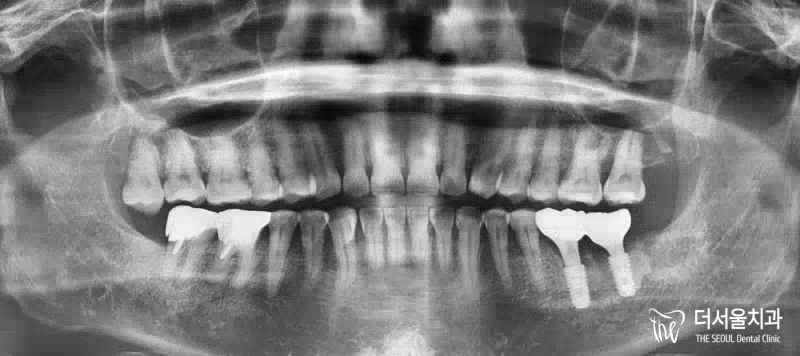

반갑습니다. 잠실 더서울 치과 입니다. 오늘 소개해 드릴 사례는 예전에 찾아오셔서 좌측 아래 어금니 임플란트 식립을 받으셨던 환자분께서 우측